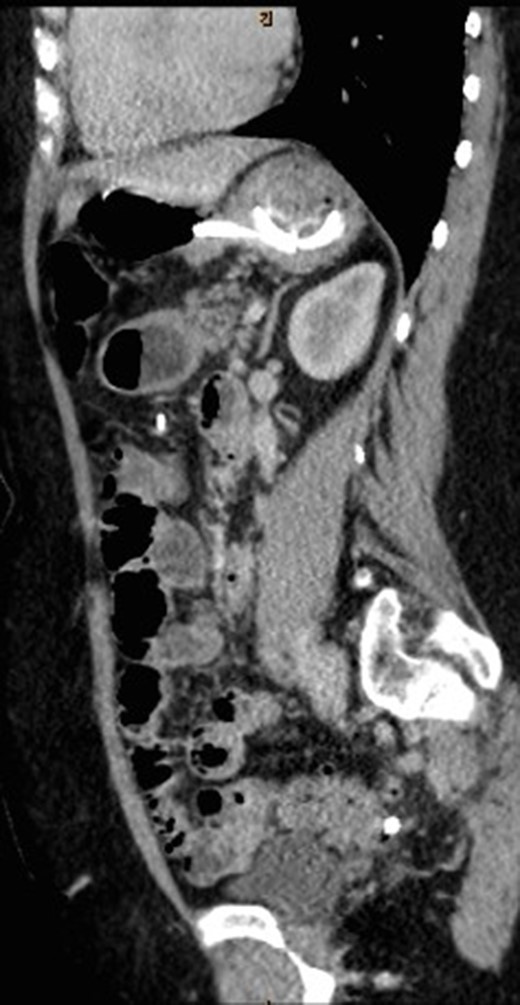

CT abdomen with oral and intravenous contrast was organized to further investigate the tubular foreign body. It revealed concurrent gastric band erosion into gastric lumen and connection tubing eroding into the posterior wall of transverse colon and exiting inferiorly (Figs 2–6). There was no evidence of any oral contrast leak from the stomach.

Sagittal view of CT abdomen showing the gastric band tubing eroding into posterior wall of transverse colon and exiting inferiorly.